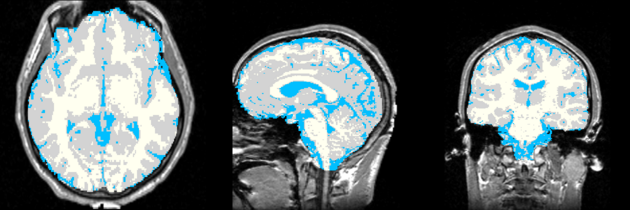

| Template (T1) | CSF | GM | WM |

Result